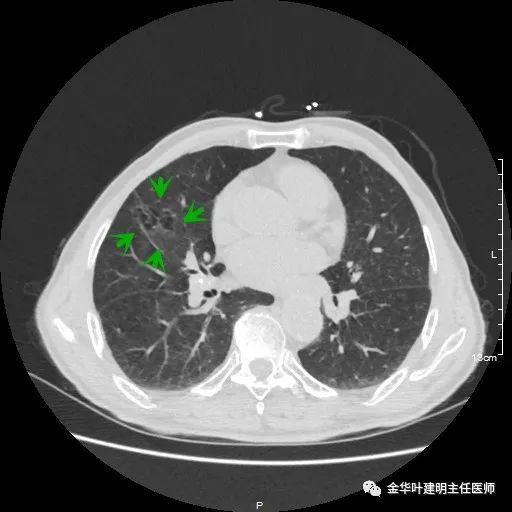

以上示右肺中叶病灶3。是混合磨玻璃结节,位置差,邻近肺门部,无法局部楔形切除,抗炎治疗后靶扫描显示了更清楚的细节,是典型的肺癌影像特征(此处未另提供)。从单病灶来看,需要行右肺中叶切除并清扫淋巴结才能得以治疗。